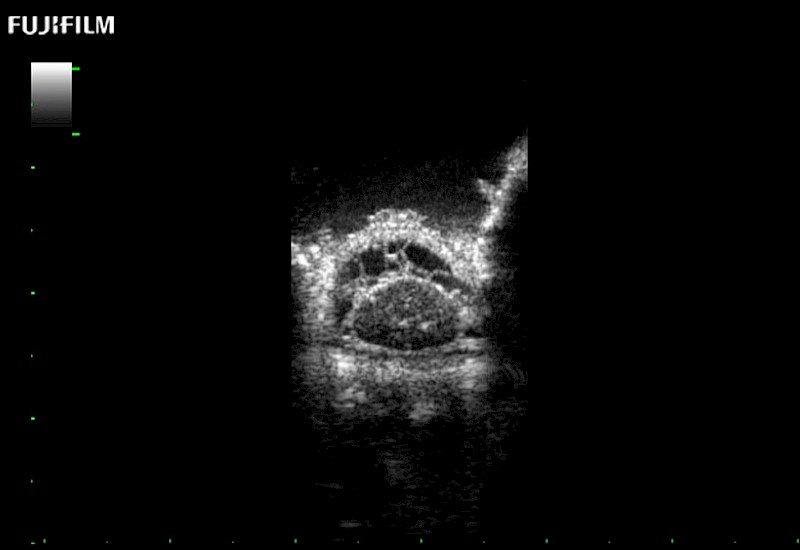

The world's only phased array burr-hole transducer that is ideal for scanning during burr-hole guidance procedures.

Main Specifications: